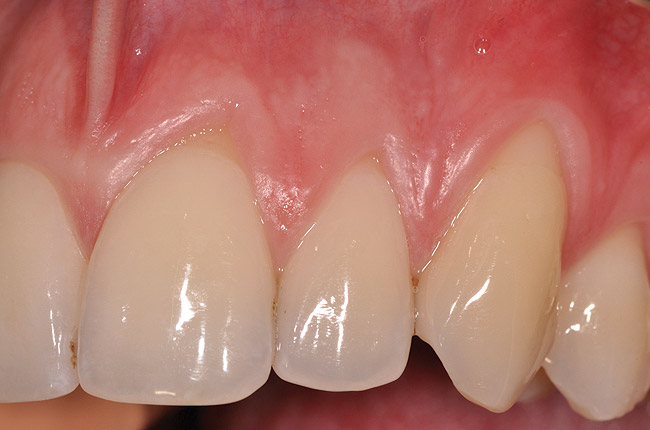

Fig 2. Post-treatment clinical view after subepithelial connective tissue graft.

Figure 2

Various procedures to correct deficient gingival contours have been well documented in the dental literature.1,2 Increasing zones of attached gingiva using palatal donor tissue and the free gingival grafting procedure was introduced by Björn almost a half century ago.3 Using palatal donor tissue in the form of a free soft-tissue autograft for root-coverage procedures was reported by Miller.4 Additional procedures were reported using lateral5 or coronal repositioning6-8 of the adjacent attached gingiva via a pedicle flap or the coronal repositioning of previously grafted tissue.9,10 Miller also reported on gingival grafts placed over root surfaces to correct areas of deep-wide gingival recession.11 Further surgical advancements led to the use of subepithelial connective tissue from the palate to obtain root coverage.12-14 Figure 1 shows the pretreatment view of a mandibular central incisor, and Figure 2 depicts the post-treatment view of the site treated with a subepithelial connective tissue graft harvested from the patient’s palatal tissues.